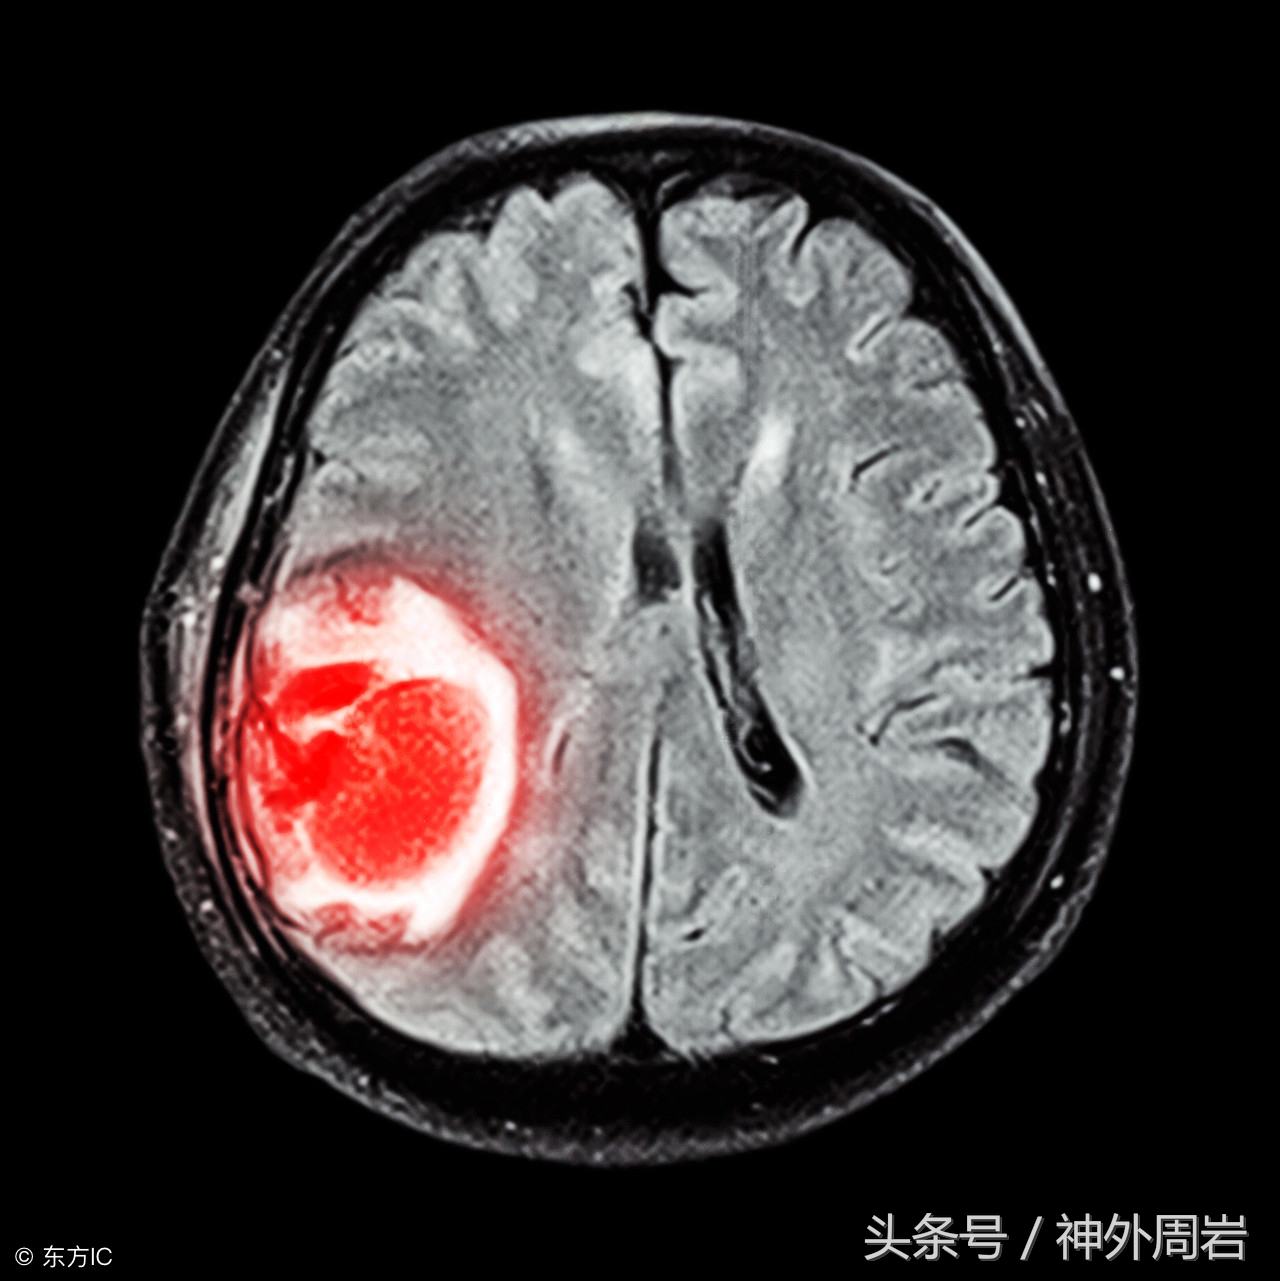

考虑到CAR-T疗法的成功,人们很容易考虑这种方法是否适用于其他癌症,尤其是那些众所周知难以治疗的癌症,如脑瘤。不幸的是,尝试并不成功,原因在于癌症本身。

癌症不仅仅是一种疾病,而是多种疾病的综合体,每一种都需要不同的治疗,脑瘤治疗的预后很悲惨,最高等级的胶质母细胞瘤患者在确诊后平均生存率为1年。

而在高级别脑癌中,由于癌细胞扩散和生长速度更快,且肿瘤呈异质性,这意味着肿瘤细胞上的目标分子在疾病的演变过程中不断变化。在同一肿瘤的不同区域,你会有不同的目标分子,所以制造一个CAR-T细胞来攻击肿瘤成为不可能的任务。

此外,高级别脑瘤建立了自己的血管网络系统,在肿瘤生长并扩散到大脑其他区域时,血管网络将支持和供给肿瘤养分,这一过程被称为血管生成。